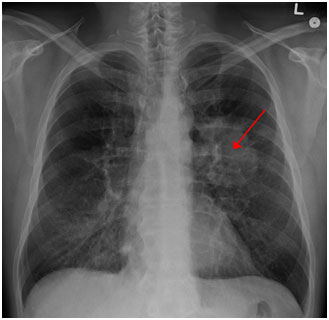

圖示:胸片上可見肺癌。(來源:James Heilman醫(yī)學(xué)博士/維基百科)